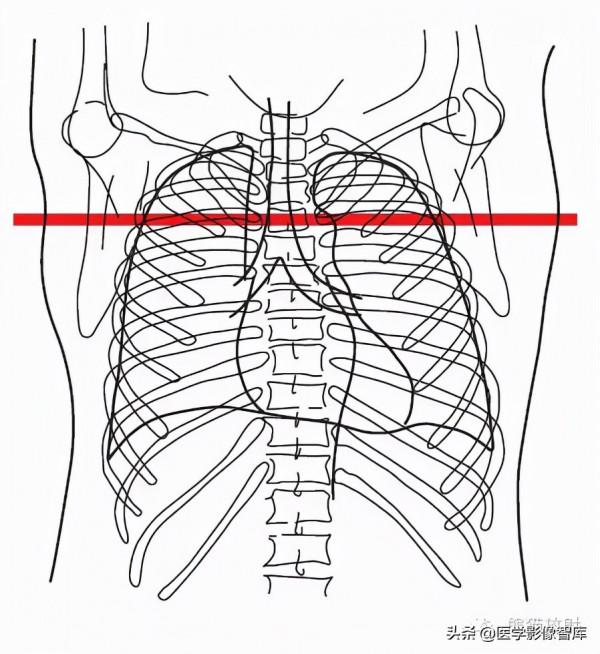

第十四層:肝靜脈水平

4. Right hepatic vein 肝右靜脈

5. Inferior vena cava 下腔靜脈

6. Left hepatic vein 肝左靜脈

7. Diaphragm 膈肌